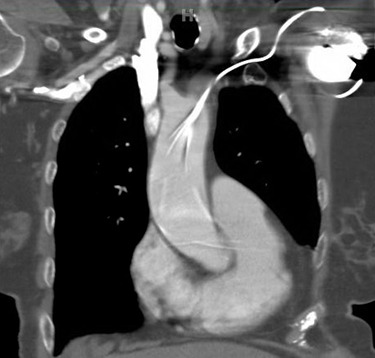

She presented to the authors’ hospital one month later with an episode of left-sided weakness, slurred speech, and the patient was diagnosed with a transient ischemic attack (TIA). Cardiology and neurology consults were obtained. She had been receiving warfarin for her atrial fibrillation and her international normalized ration (INR) on admission was at a therapeutic level. The authors could not exclude transient subtherapeutic INR levels leading to clot formation and thromboembolic phenomenon from her atrial fibrillation. However, her electrocardiogram (ECG) demonstrated an abnormal finding that provided an important clue for the etiology of her presenting symptoms. Her ECG demonstrated a ventricular paced rhythm with a right bundle branch block pattern (Figure 1). A chest x-ray was performed that demonstrated misplacement of the single lead pacemaker with an atypical posterior curvature path. A computerized tomography (CT) scan was performed which further demonstrated her misplaced single-lead pacemaker traversing the aortic valve into the LV (Figure 2).